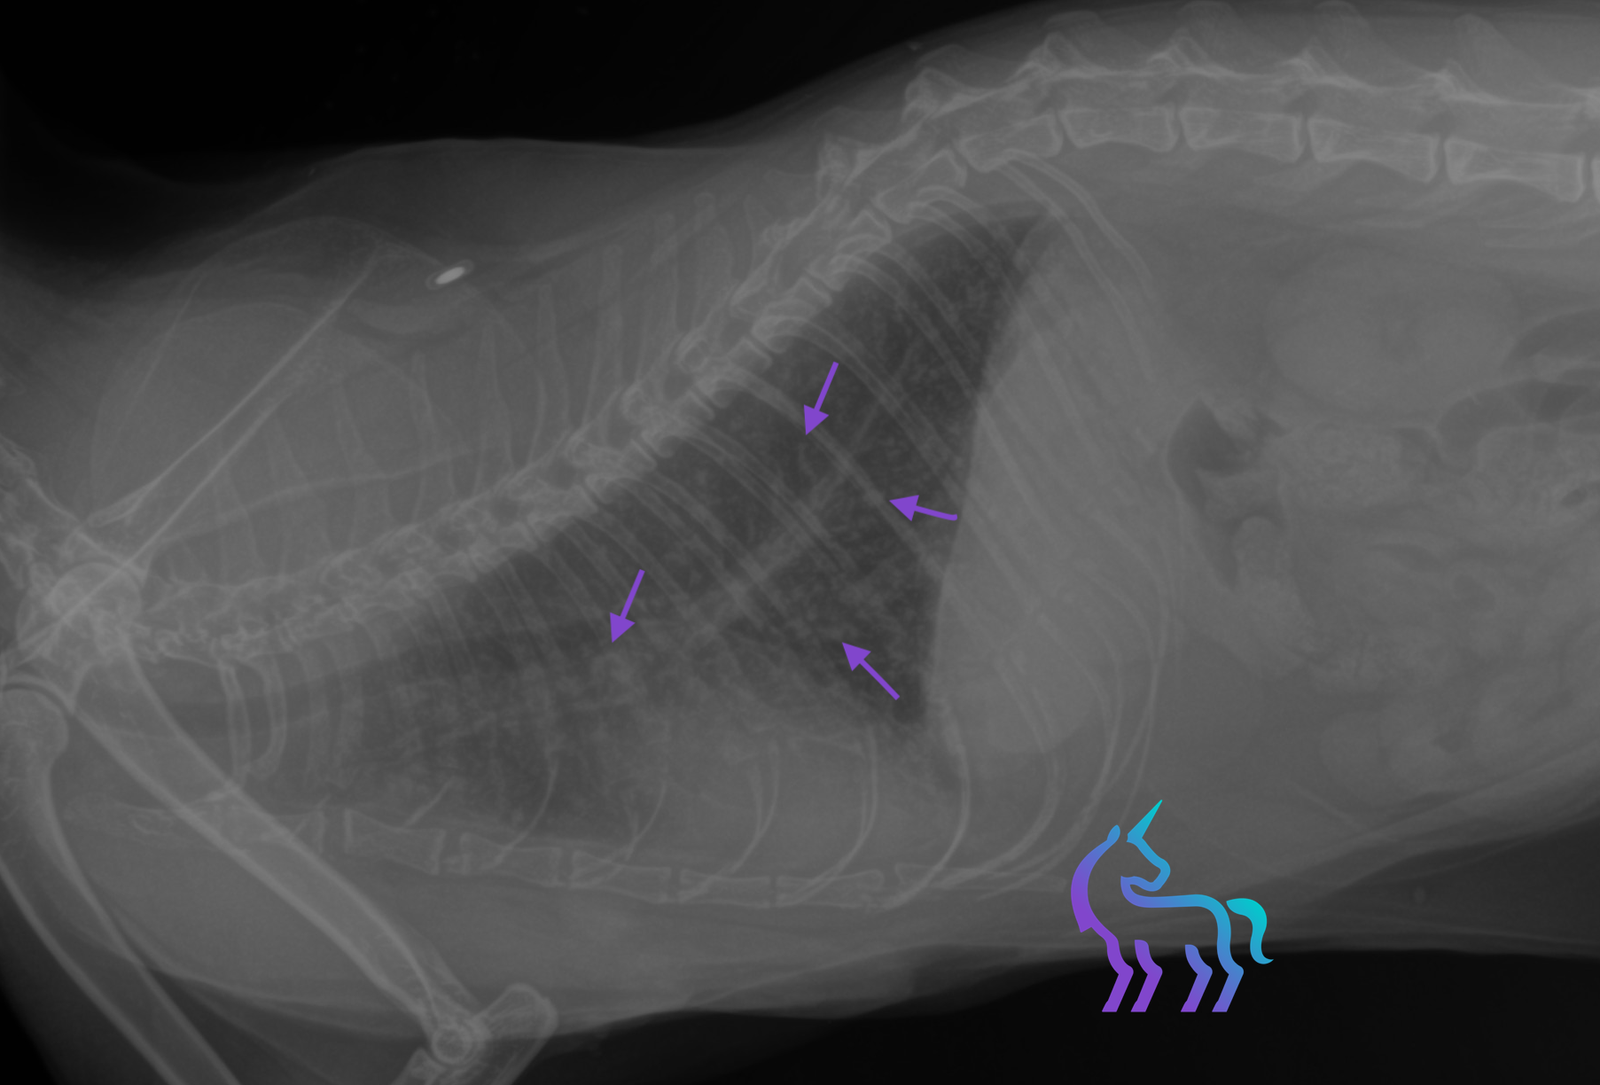

Dissémination métastatique pulmonaire (Aspect miliaire)

Espèce : ChatRadiographies thoraciques montrant de multiples nodules pulmonaires millimétriques diffus, donnant un aspect miliaire sur l’ensemble des lobes.

L’ensemble est compatible avec des métastases pulmonaires, dans un contexte de récidive de tumeur mammaire.

Diagnostic retenu : La radiographie permet ici de poser un diagnostic de dissémination métastatique pulmonaire et de contre-indiquer la chirurgie.